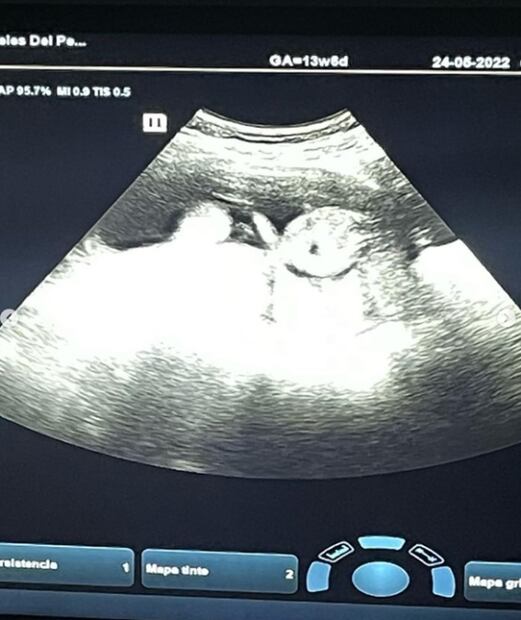

“Qué mejor día para compartir esta noticia con toda mi gente querida que hoy. Para mi hijo (a): aún no sabemos si serás un niño o una niña, pero lo que puedes tener por seguro es que ya te amamos”, escribió junto a la fotografía del primer ultrasonido de su pequeño.

Foto: Instagram